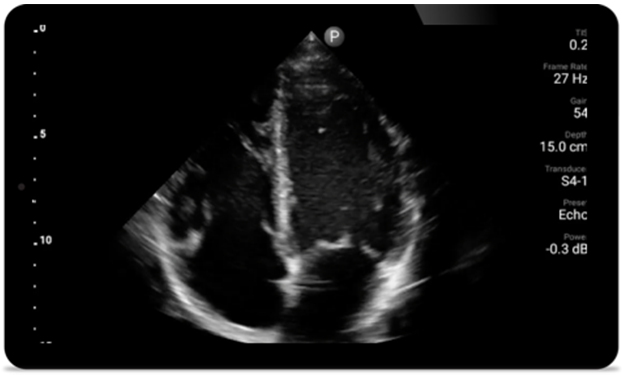

Gdy liczy się każda sekunda — diagnostyka kardiologiczna

Pacjenci, u których doszło do zawału serca, wymagają pilnego leczenia. Dostępne w systemie Lumify ustawienia do badań serca mogą przyspieszyć ich zdiagnozowanie, a w konsekwencji poprawić wyniki ich leczenia.

• Rozszerzony zakres częstotliwości roboczej od 4 do 1 MHz • Obrazowanie 2D, kolorowy Doppler, tryb M-mode, zaawansowana technika XRES oraz wielowymiarowe obrazowanie harmoniczne • Obrazowanie w wysokiej rozdzielczości do badań jamy brzusznej i serca: optymalizacja ustawień predefiniowanych obrazowania serca, badań położniczo-ginekologicznych, płuc, jamy brzusznej oraz protokołu FAST System Lumify pomaga ratować życie w warunkach przedszpitalnych